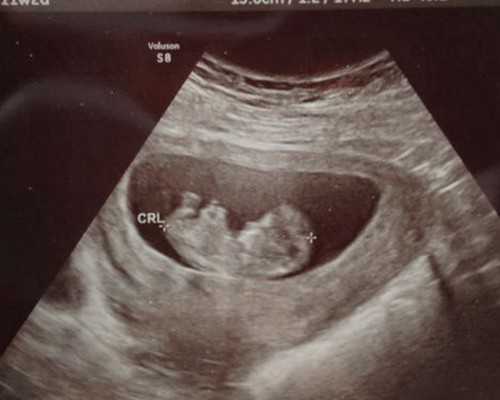

生活在21世纪,其实不管是男性还是女性,其工作和生活等方面都有一定的压力。特别是对于女性来说,因为受到饮食和空气等影响,造成很多人出现不孕不育症,所以这种情况只能接受试管婴儿治疗助孕。

试管婴儿可以说是一项新兴技术,它的费用比较高,但人们除了关心费用问题之外,还有与它相关的弊端。也就是说,每项手术都有相对应的利弊,而试管婴儿也是同样的道理。那么试管婴儿的弊端有哪些呢?

每一项新事物的出现必然会引起很多的争议,试管婴儿技术的出现也一直备受关注,一开始试管婴儿的出现可能引起了很多人的误解,后来随着做试管的人越来越多,试管婴儿技术不断成熟,到今天已经逐渐被接受。目前,世界上已经有超过800万例试管婴儿诞生,平均每100个诞生的宝宝中就有1例是试管宝宝。不管任何事物都是有它的两面性,试管婴儿技术也是一样,今天主要来聊聊试管婴儿的利弊问题: